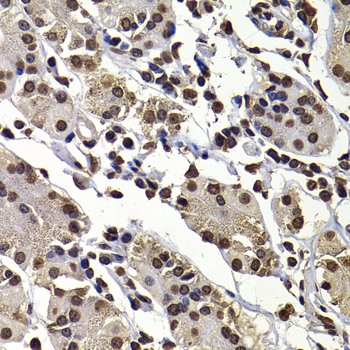

Immunohistochemistry of paraffin-embedded human kidney cancer using DNAJB6 antibody at dilution of 1:100 (x400 lens).